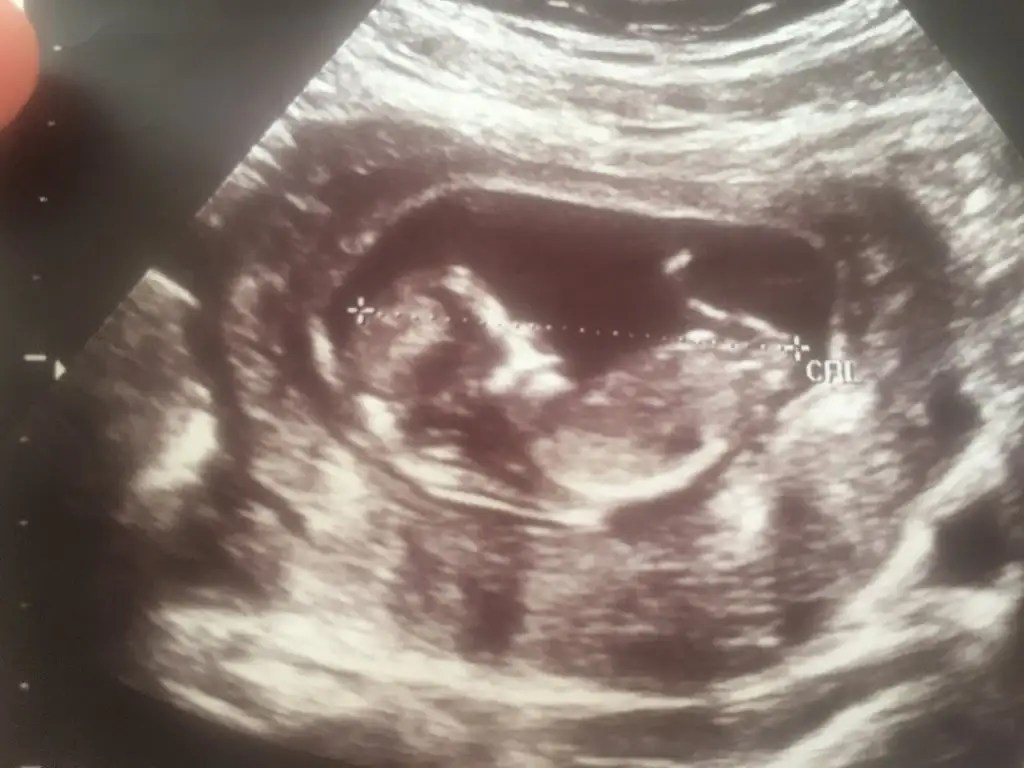

Benim için de tahmin yürütür müsünüz?

• IMG_20210220_141757.webp

IMG_20210220_141757.webp

20,4 KB · Görüntüleme: 159